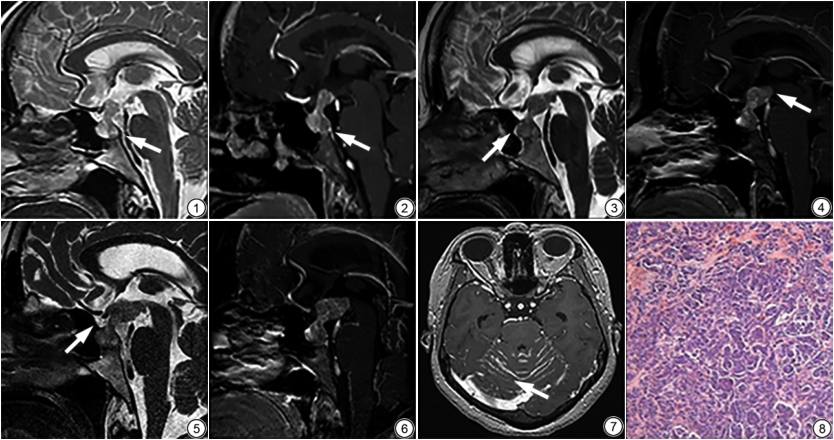

MRI检查:第一次垂体平扫+动态增强:蝶鞍扩大,鞍底下陷,鞍膈抬高,其内信号不均,神经垂体高信号消失,呈等T1WI等T2WI。垂体柄居中,增粗。垂体及垂体柄明显不均匀强化,动脉期强化明显,延迟期减退;第二次3个月复查垂体:病灶较前增大,累及垂体前叶及下丘脑;第三次4个月复查垂体:视交叉结构受累,T2WI可见高信号;双侧颞叶,枕叶,小脑半球软脑膜可见增厚强化;第四次4个月头颅平扫+增强:较前相仿,未见明显弥散受限。4个月头颅CT血管造影(CT angiography,CTA)检查:鞍区及鞍上区类圆形稍高密度影,增强后明显不均匀强化。

MRI是鞍区病变的首选检查,尤其是冠状位与矢状位。可以观察垂体的形态、大小和信号改变,血供特点,浸润范围及与周围组织间的关系,骨质受侵情况等。PM主要的影像表现为:(1)多发生在垂体柄和/或垂体后叶;(2) CT多表现为稍高或等密度;(3) MRI多呈肿块骑跨鞍膈,向鞍内和鞍上生长,形似束腰征[5],垂体柄增粗,多不对称;(4) T1WI常见垂体后叶高信号消失,可见残存的垂体前叶组织;(5)垂体周围结构受累明显,可侵犯漏斗隐窝;(6)增强早期多呈明显不均匀强化,延迟期强化程度下降[6]。在影像上需要与以下疾病相鉴别:(1)LYH:多发于产后或妊娠后期女性,影像鉴别要点包括:①垂体柄:LYH为弥漫性、对称性垂体增大,垂体柄居中,转移癌多偏移;②MR信号:垂体后叶高信号消失,而垂体炎信号较均匀,边界更模糊。③强化表现:LYH增强呈明显均匀强化,累及硬脑膜后增强出现的硬脑膜尾征是LYH的征象之一[7],PM强化常表现为“快进快出”不均匀强化。④与周围结构关系:LYH常局限于垂体内,PM常侵犯邻近结构。本例患者初期检查垂体柄增粗居中,神经垂体高信号消失等易与LYH混淆,但强化方式有利于鉴别,PM早期不均匀明显强化,延迟快速廓清,LYH强化较均匀,边界更模糊,廓清较慢。另外,LYH有自发缓解倾向,免疫抑制或激素治疗有效[8],该患者甲强龙治疗1个月后症状无改善反而加重。再有,发病人群可用于鉴别,该患者有肿瘤病史,不能轻易排除转移的可能,而LYH易发于产后或妊娠后期女性。(2)垂体腺瘤:年轻女性多见,多发生于腺垂体,神经垂体不受累。垂体腺瘤多引起垂体柄的推压、偏移中线,但垂体柄本身多不受累。动态增强早期强化低于正常垂体,延迟扫描等或高于垂体。最常见的垂体腺瘤是泌乳素瘤,多巴胺受体激动剂疗效显著。PM可查出原发病灶,相同大小病灶较垂体炎、腺瘤病情进展更快,症状更严重,短期内可突破鞍膈,侵及邻近结构。本例患者免疫组化Her2 (3+),Ki-67 (30%+),表明肿瘤低分化恶性程度高,增殖旺盛,可以解释短时间内进展迅速。PM患者全身状况差,早期出现尿崩症是鉴别PM与垂体腺瘤的最重要依据。